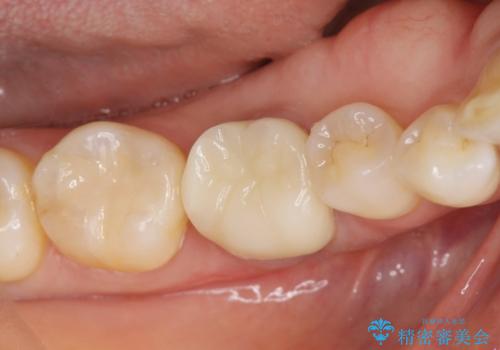

- 長年気になっていた、目立つ銀歯を白くしたい。とセラミック治療を希望され来院されました。

銀歯を除去したのち、精度の良いジルコニアセラミッククラウンでクラウンのやり替えを行っていきます。

目立っていた銀歯が自然な白い歯となり、長年のコンプレックスが解消されたと満足いただくことができました。